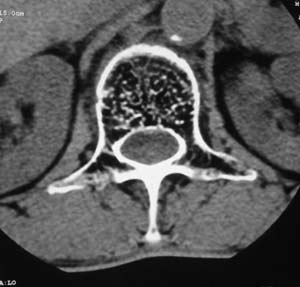

以下是引用余辉在2008-4-27 17:12:00的发言:[br]骨质疏松伴病理性压缩性骨折,椎骨骨松质密度减低,椎体骨小梁稀疏且普遍呈火柴头样改变,椎体无膨胀,无软组织肿块

以下是引用mzh123在2008-4-27 19:33:00的发言:[br]除压缩骨折表现外 还有许莫氏结节改变

以下是引用随光逐影在2008-4-27 21:29:00的发言:[br]除压缩性骨折外,还有许莫氏结节及骨质疏松表现。